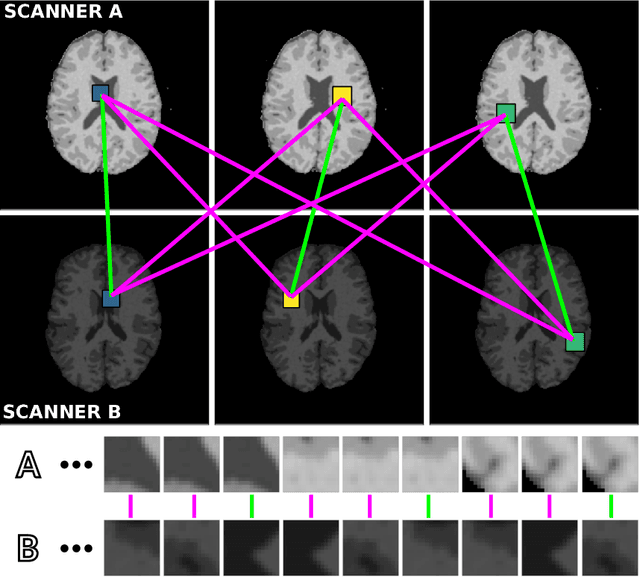

Abstract:Generalization of voxelwise classifiers is hampered by differences between MRI-scanners, e.g. different acquisition protocols and field strengths. To address this limitation, we propose a Siamese neural network (MRAI-NET) that extracts acquisition-invariant feature vectors. These can consequently be used by task-specific methods, such as voxelwise classifiers for tissue segmentation. MRAI-NET is tested on both simulated and real patient data. Experiments show that MRAI-NET outperforms voxelwise classifiers trained on the source or target scanner data when a small number of labeled samples is available.

Abstract:Voxelwise classification approaches are popular and effective methods for tissue quantification in brain magnetic resonance imaging (MRI) scans. However, generalization of these approaches is hampered by large differences between sets of MRI scans such as differences in field strength, vendor or acquisition protocols. Due to this acquisition related variation, classifiers trained on data from a specific scanner fail or under-perform when applied to data that was acquired differently. In order to address this lack of generalization, we propose a Siamese neural network (MRAI-net) to learn a representation that minimizes the between-scanner variation, while maintaining the contrast between brain tissues necessary for brain tissue quantification. The proposed MRAI-net was evaluated on both simulated and real MRI data. After learning the MR acquisition invariant representation, any supervised classification model that uses feature vectors can be applied. In this paper, we provide a proof of principle, which shows that a linear classifier applied on the MRAI representation is able to outperform supervised convolutional neural network classifiers for tissue classification when little target training data is available.